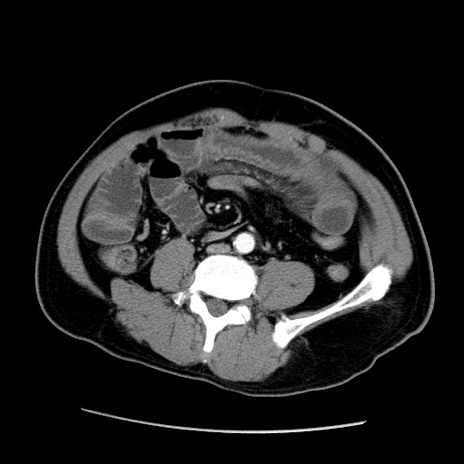

症例22(横断像)

【症例】50歳代男性

【主訴】腹痛

【現病歴】AVMからの被殻出血のため回復期リハ病棟入院中。 本日午後3時頃急に下腹部痛が出現した。

【既往歴】AVM、被殻出血、虫垂炎、高血圧

【身体所見】意識晴明、左半身不全麻痺、会話の理解は良好、36.5°C、腹部:膨隆、全体に板状硬、下腹部正中に圧痛点あり、反跳痛-、筋性防御不明、右下腹部にope scar

【データ】WBC 9400、CRP 0.06